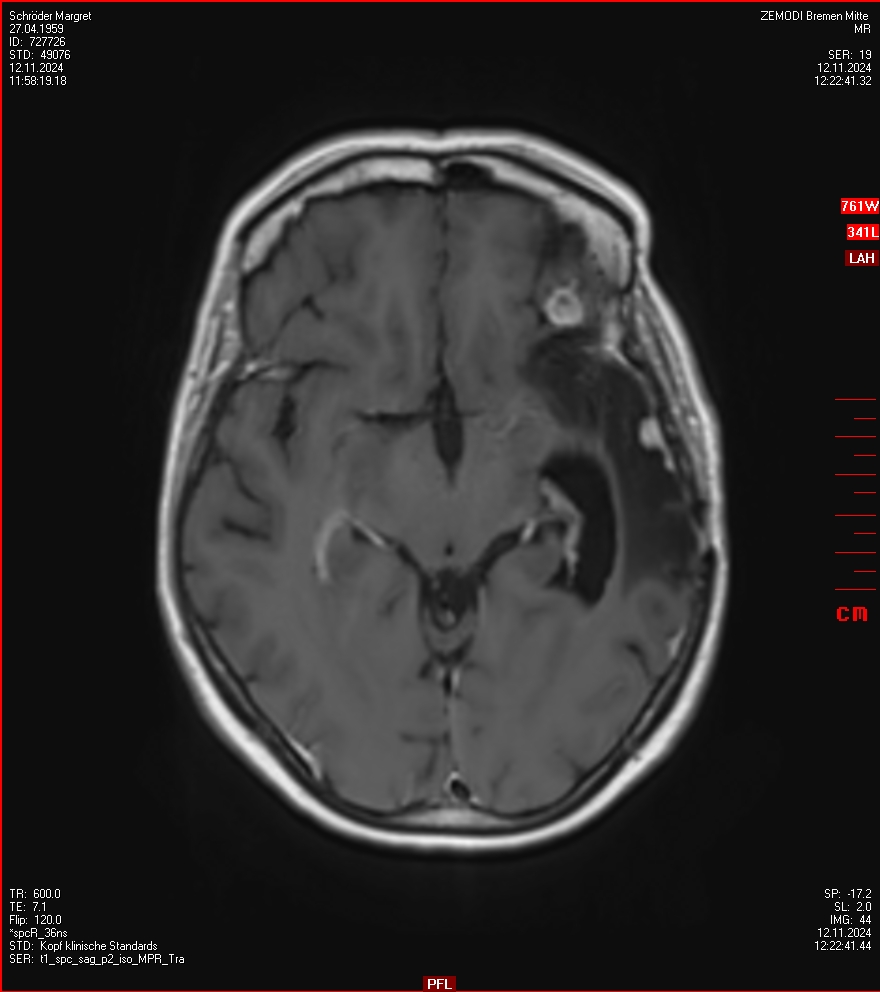

MRT vom 12. November 2024

So nun ein paar neue Bilder aus meinem Kopf. (Durch klicken bekommt man eine größe Ansicht eines Einzelbildes).

Die letzten drei Bilder Zeigen aus meiner Sicht den Tumor, der im Jahr 2021 bestrahlt wurde.

Ich denke, in den letzen 12 Monaten sind da ein paar Rezidive gewachsen,  vor 12 Monaten waren sie auch schon zu erkennen - vorher noch nicht. Nun hoffe ich auf den Rat des Spezialisten. Hoffendlich kann man etwas machen.